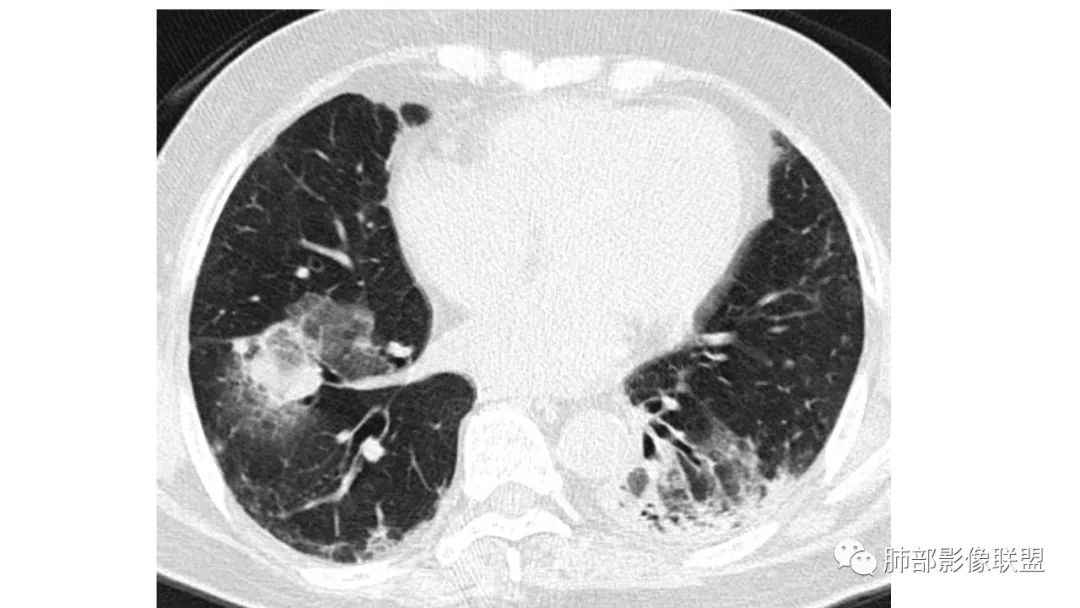

二、肺炎型

2、病灶常有一个主病灶,常位于下肺。后沿气道播散为多发病灶。

3、重力作用,叠瓦征。近叶间裂因重力效应,呈膨隆改变。

4、增强后不均匀强化,存在低强化区呈弱强化或无强化,因此可见“血管造影征。”血管毛糙与肺炎有统计学差异。

5、支气管粗细不均,呈“枯树枝征”,但与肺炎这一点鉴别不具有统计学差异。可发生支气管扩张

6、空腔形成,部分蜂窝状改变。

8、斑片常伴有结节,边缘清楚GGO或欠清楚。